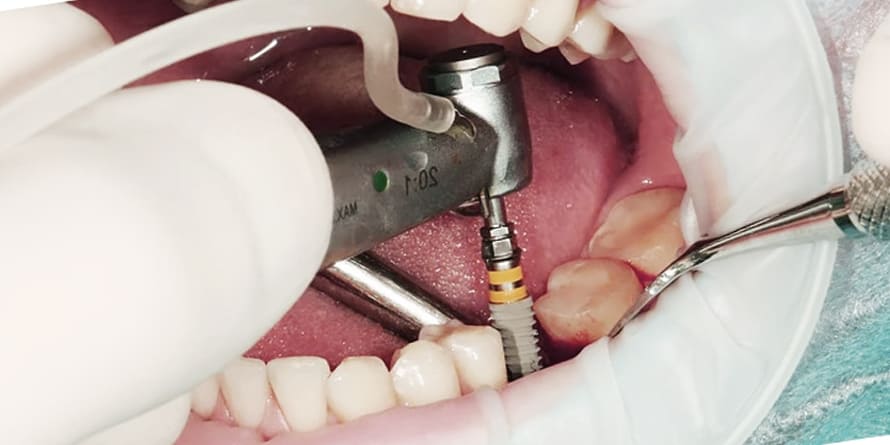

최근에는 3차원 CT스캔을 이용해 자신의 치아 상태에 최적화된 임플란트를 만들 수 있을정도로 꼼꼼한 진단과 세심할 시술이 가능하니 적응할 수 있을까 라는 걱정은 하지 않아도 됩니다.